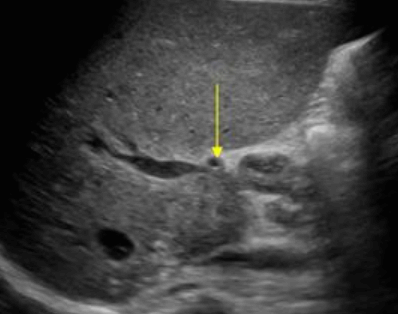

US finding

- 간내담관은 확장되고 간외담관은 정상이다.

- 담낭은 위축되며, 간외담관은 담즙 흐름이 없는 담관으로 묘출된다.

- 폐쇄된 담관부위에 종양의 윤곽이 보일 수 있으나 초음파상 발견하기 어렵다.